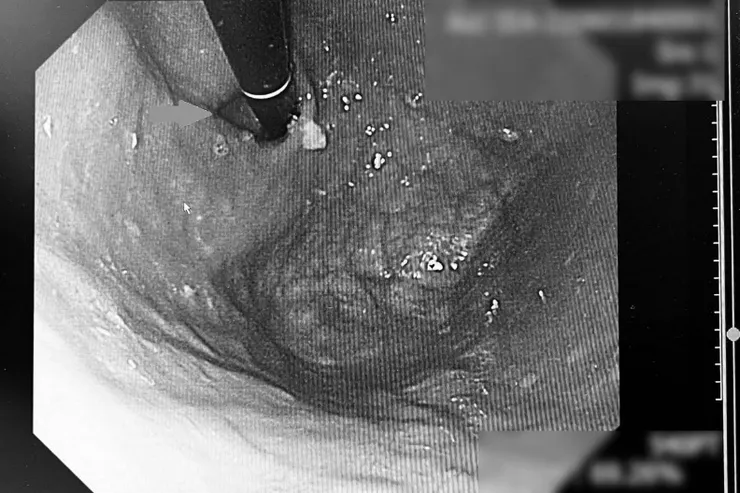

要避免癌化就要治根治本,當橫膈膜疝氣的病人來到消化外科,醫師會透過腹腔鏡手術的三個微小切口來修補疝氣,同時施以「胃底摺疊術」,將賁門附近的胃組織包覆於下食道外圍,藉此改善胃與食道交接處肌肉的鬆弛情形,緩解逆流。

而手術摺疊的方式有兩種,傳統方式是將食道做360度的包圍,這種方式雖然效果好,但約有15%的病人在術後出現吞嚥困難、胃脹、打嗝的副作用,相當考驗醫師對食道的鬆緊度拿捏;而改良式手術則是以270度的範圍包覆食道,留有食道空間,避免了吞嚥困難及脹氣的困擾。